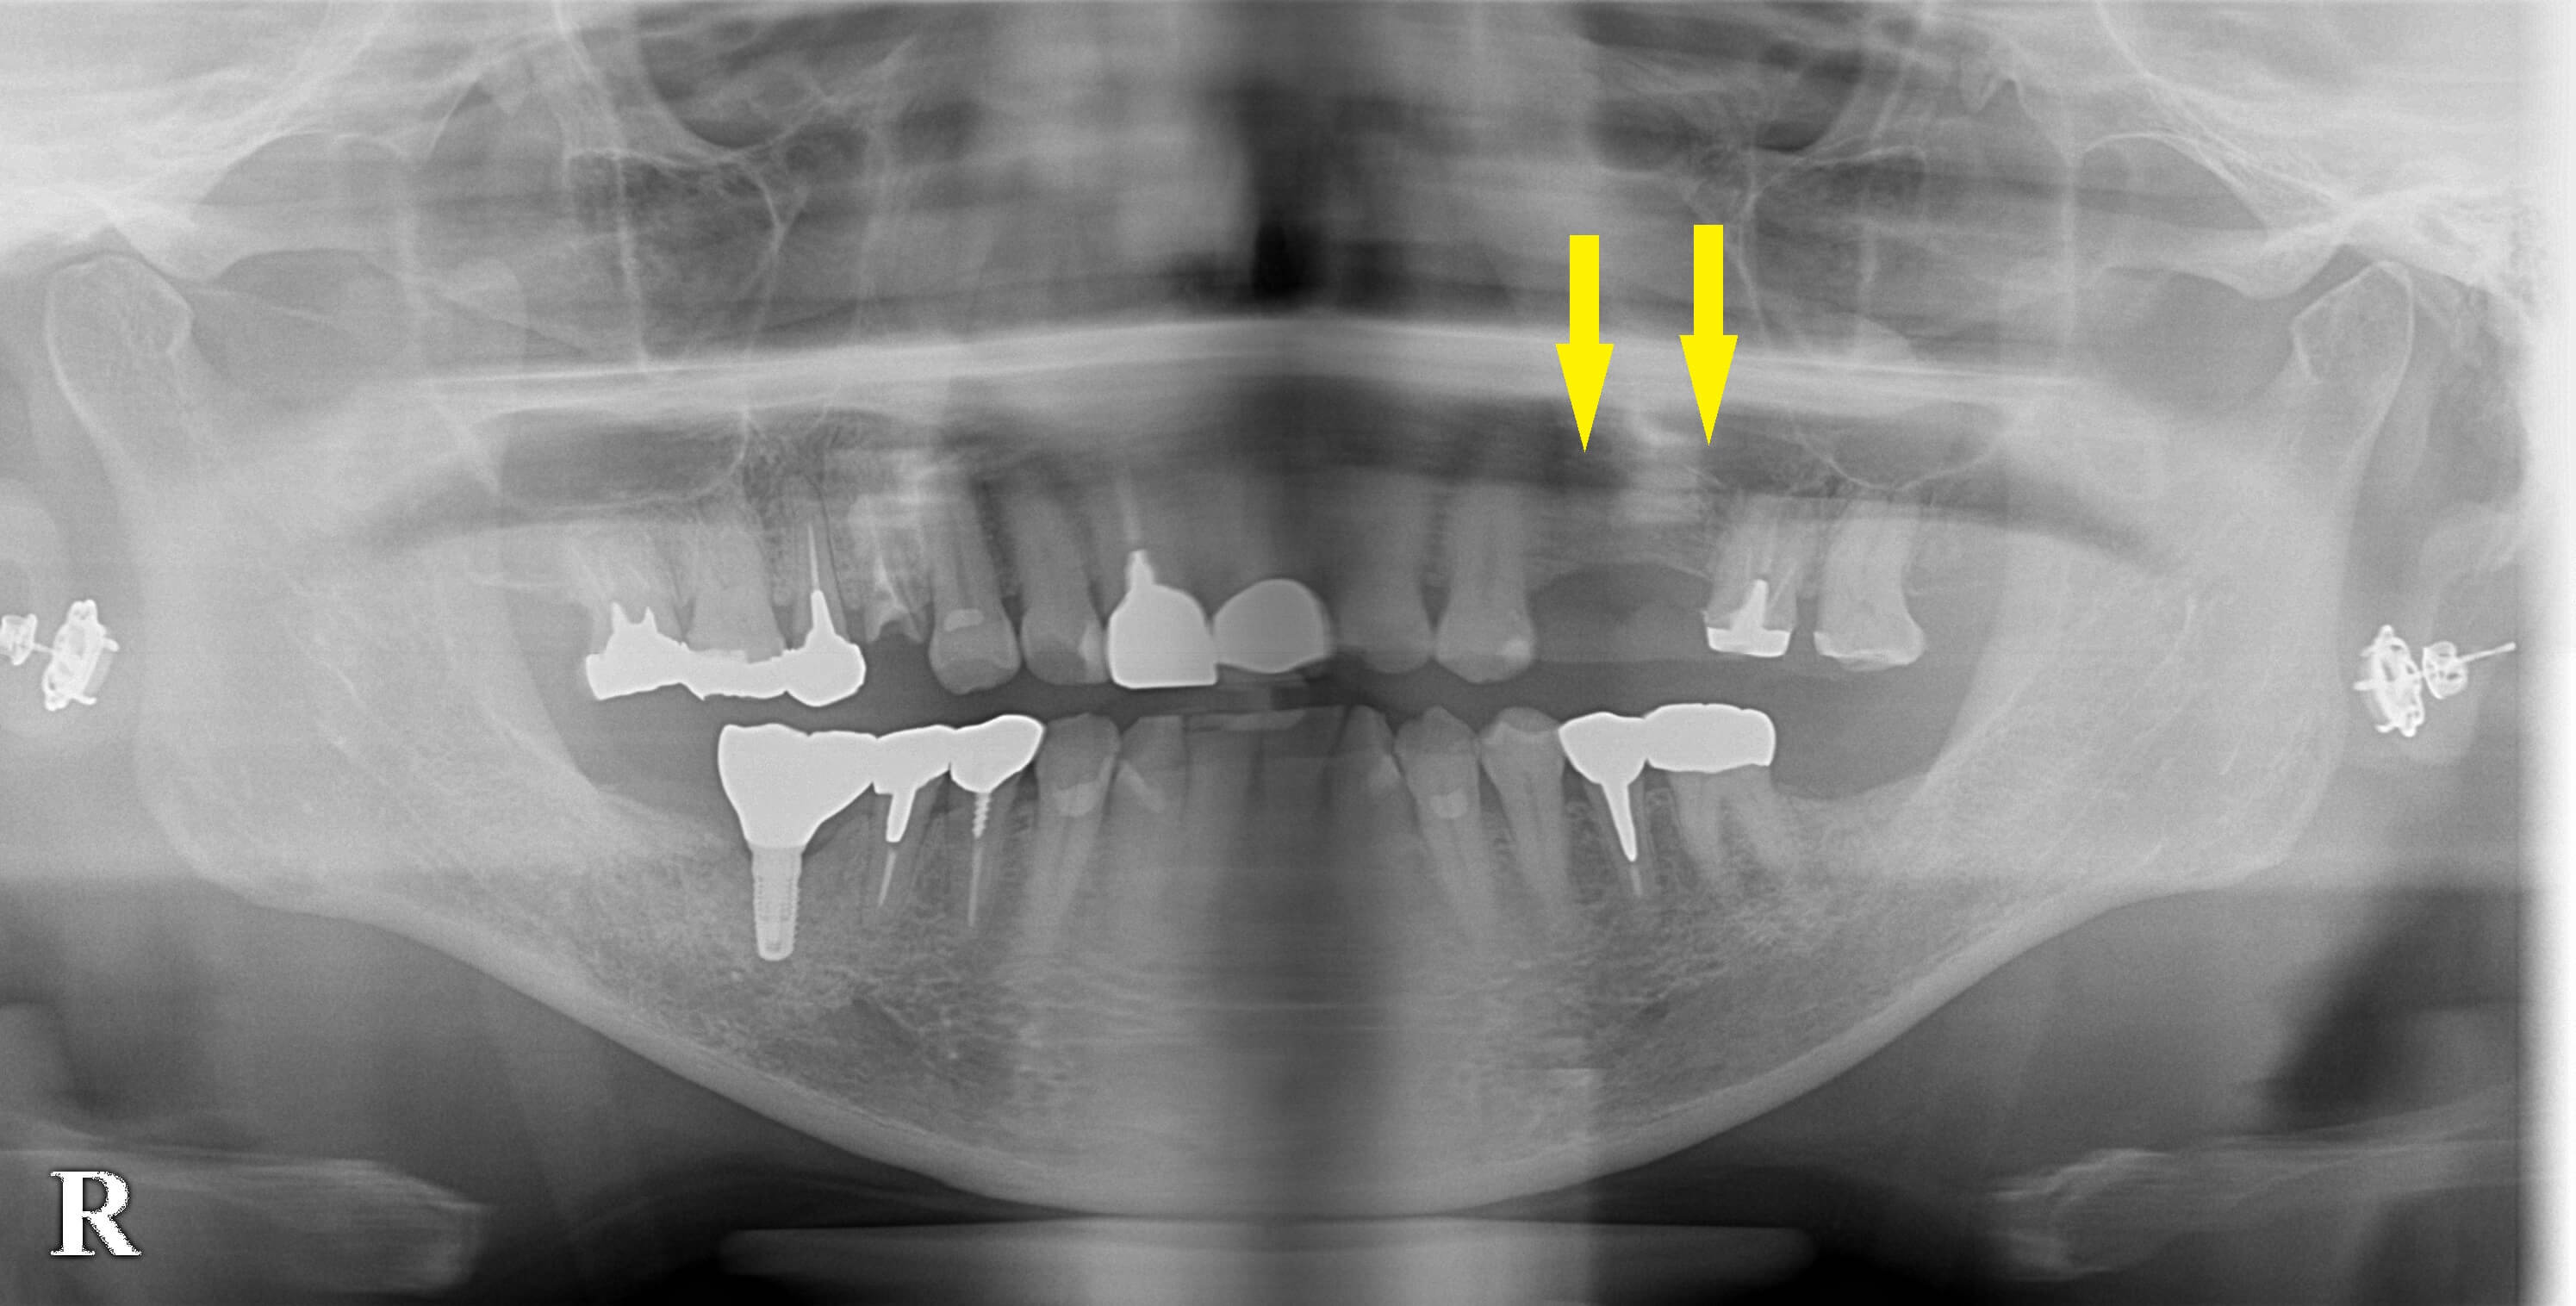

CTを撮ってみると、骨の高さはあるのですが、幅が薄くて、通常のインプラント埋入はできなさそうでした。

骨幅を拡げる骨造成手術を併用すれば、インプラント治療が可能であることを説明し、同意が得られましたので本日手術となりました。

インプラント埋入と同時に、頬側(外側)に人工骨を填入して、さらに人工膜で被覆するという骨造成術(GBR)を施行しました。

下の写真、下段左が手術前のCTです。骨が三角に切り立っています。右が手術後のCTです。

インプラントが骨に埋入され、その外側に填入した人工骨が認められます。